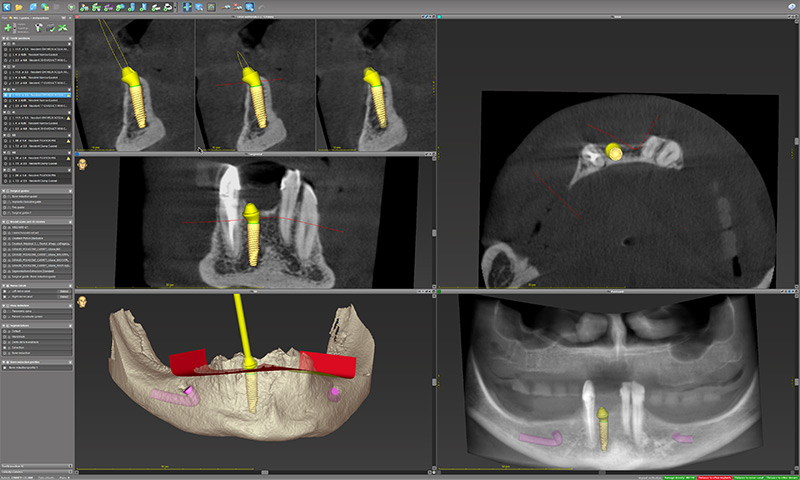

Fig. 16, 17 et 18.

Le modèle virtuel de travail est débarrassé de tout le superflu pour déterminer virtuellement le plan de résection osseuse matérialisé en rouge (fig. 16). La régularisation est validée implant par implant et dans tous les sens de l’espace (fig. 17) avant d’être virtuellement soustraite de la crête (fig. 18).

Fig. 19 : premier guide qui reproduit l’ostéotomie.

Un premier guide claveté par 3 pins est dessiné à reproduire sur la mandibule de la patiente l’ostéotomie déterminée numériquement précédemment.

Fig. 20 : création d’un second guide.

Un second guide est créé, empilé sur le précédent pour réaliser le forage et la pose des implants.

Fig. 21 : clonage de la prothèse diagnostique.

La restauration transitoire empilée sur le guide de résection est designée par clonage de la prothèse diagnostique.

Toute la subtilité du concept réside dans le fait que le guide de réduction solidement claveté sert de repère orthonormé à la restauration transitoire pour permettre son repositionnement sans aucune perturbation.

Fig. 22 : forage des emplacements des pins.

Enfin, afin de s’assurer du bon positionnement du guide de résection, un dernier guide permet le forage des emplacements des pins en fonction des structures initiales.

Fig. 43 : les implants (Neodent GM Helix Acqua, Straumann Group) et les piliers (Mini GM) sont planifiés selon le projet numérique virtuel.

Fig. 44 et 45 : un plan de réduction osseuse est arbitrairement déterminé pour créer un guide de résection sur le STL du masque gingival.

Fig. 46 et 47 : l’objectif du guide dans ce deuxième cas qui ne nécessite pas de réduction osseuse est simplement de servir de support et de repère à la mise en place du guide implantaire et de la prothèse transitoire.

Fig. 48 : une fois encore, un guide de forage est conçu pour matérialiser les emplacements des pins en fonction des structures initiales.